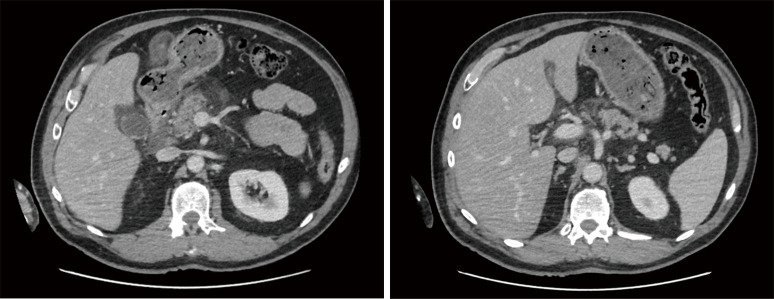

Case description: Here, we present a case of a 61-year-old male, admitted to emergencies with severe abdominal pain and one episode of vomiting. The patient initially diagnosed with mild acute pancreatitis and probable cholecystitis. Because of its severe clinical picture, the patient was admitted to our intensive car unit. Subsequent imaging revealed progression to gangrenous cholecystitis. Decision was taken to drain the gallbladder under computed tomography (CT) scan. Despite antibiotic therapy, the patient developed acute respiratory distress syndrome (ARDS), necessitating intubation. Upon stabilization, an exploratory laparoscopy revealed infected necrosis of the falciform ligament, prompting resection and drainage. Postoperatively, the patient presented a progressive clinical and biological amelioration. The drain was removed and the follow-up was uneventful. A laparoscopic cholecystectomy was scheduled 3 months later.

Conclusions: FLN poses diagnostic challenges due to its nonspecific symptoms and tendency to mimic other abdominal pathologies. Diagnostic laparoscopy emerges as a valuable tool for both confirmation and treatment, enabling necrotic tissue excision and effective drainage. This case underscores the importance of considering rare entities like FLN in the differential diagnosis of abdominal acute pain, with laparoscopic intervention offering a definitive therapeutic option.